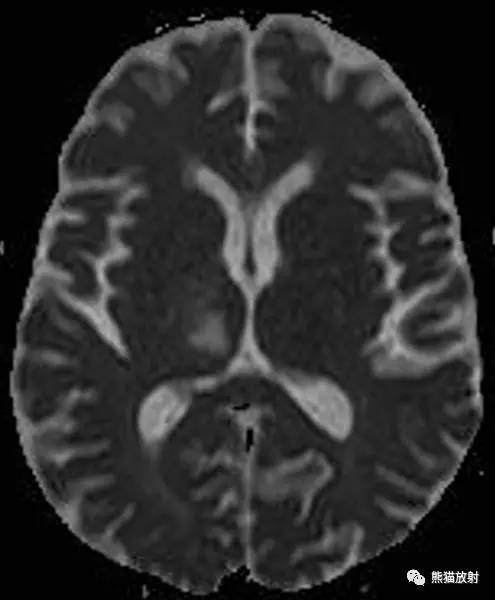

CASE 3

病史:患者女性,32 岁,因精神紊乱改变入院。

MR 图像依次为:液体恢复反转图像(FLAIR, 前三幅),弥散加权图像(DWI)、表观弥散系数图(ADC 图)和磁敏感加权图(SWI)。

CT:在双侧顶叶、枕叶皮层下白质、深部白质束和胼胝体可见多发融合的密度减低区。无占位效应,灰质密度未见明显异常。

MRI:双侧顶枕叶皮层下白质、深部白质和胼胝体区见异常 FLAIR 信号。DWI 未见弥散受限。

诊断:结合临床病史,以上影像学表现符合进行性多灶性白质脑病(PML)